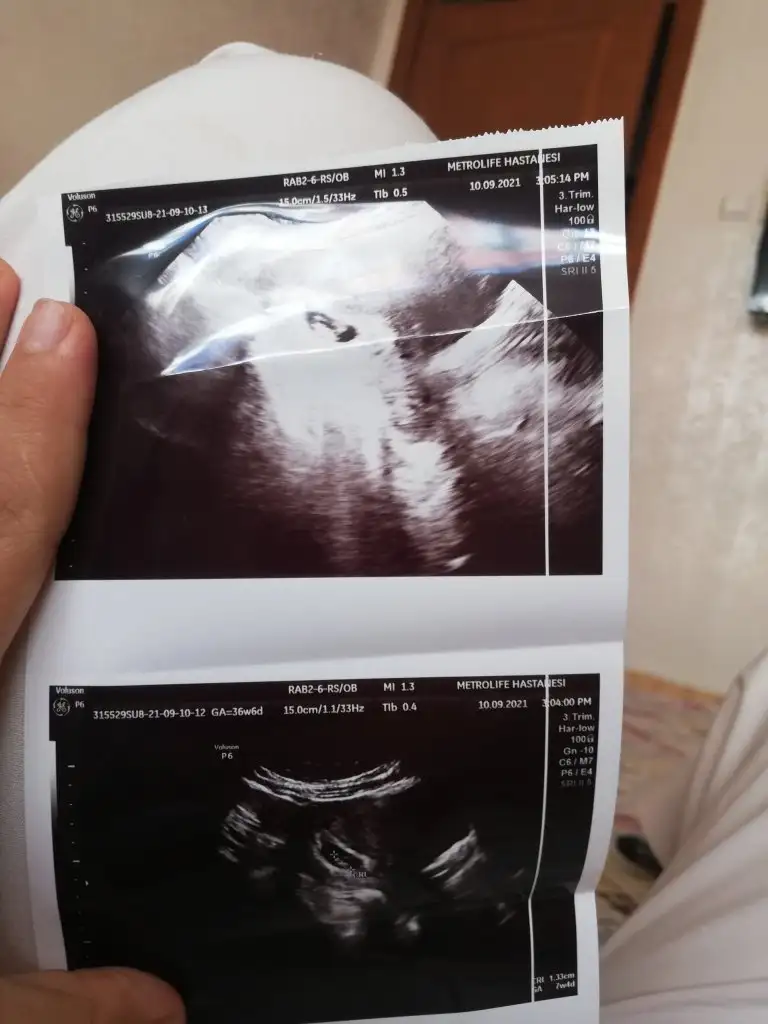

Bana da bakar mısınız 8 haftalık görüntü bu

Eklentiler

• IMG_20210910_152824.webp

IMG_20210910_152824.webp

31,8 KB · Görüntüleme: 83

• IMG_20210910_152817.webp

IMG_20210910_152817.webp

31,2 KB · Görüntüleme: 101

Merhaba arkadaşlar karından bakıldı 8 haftalık yardımcı olursanız çok sevinirim

Ramzi teorisine göre ( bilimsel bir araştırma sonucuymuş ve %85 doğruluğu varmış). İlk 6-8 haftalık ultrason görüntüsüne göre bebeğin kesenin içersinde soldan ya da sağdan girişine göre cinsiyet tahmini yapılıyor. Bilimsel olunca tecrübeli annelerimiz yada anne adaylarımızdan yardım istiyoruz. Doğruluğu var mı öğrenmek adına :) Bizleri aydınlatırsanız çok seviniriz. bu teorieye göre;

Vajinal muayeneyle bakıldıysa eğer;

Sağdan girmiş gözüküyosa aslında solmuş ve ERKEK,

Soldan girmiş gözüküyosa aslında sağmış ve KIZ ,

Karından bakıldıysa eğer,

Soldan girmiş gözüküyosa gerçektede solmuş ve ERKEK,

Sağdan girmiş gözüküyosa gerçekte de sağmış ve KIZ,

Bi teori anca bu kadar yanliş anlatilabilirdi ..arkadaşlar ramzi teorisini araştiran biri bunun doğru olmadiğini anlar ..doğru yorum yapabilmek için bebeğin konumuna gore değil plesantanin konumuna göre yorum yapılmasi gerekiyordu